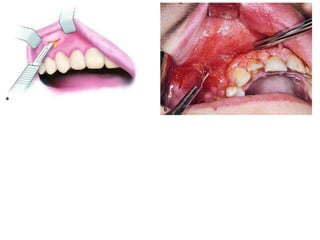

Examples of fascial

 Abscess of Base of

Upper Lip

 Etiology. It is usually caused by

infected root canals of maxillary

anterior teeth.

 Clinical Presentation.

 swelling and protrusion of the

upper lip,

 diffuse spreading and obliteration

of the depth of the mucolabial fold

Treatment

• incision for drainage:

• is made at the mucolabial fold parallel to

the alveolar process.

•A hemostat is then inserted inside the

cavity, which reaches bone, aiming for the

apex of the responsible tooth, facilitating

the evacuation of pus.

•A rubber drain is placed until the clinical

symptoms of the infection subside .